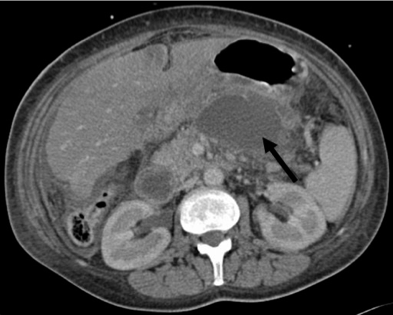

It is a circumscribed intra-abdominal collection of pus , usually in proximity to the pancreas. This is a result of infection of a pseudocyst. It need urgent drainage.

It is a circumscribed intra-abdominal collection of pus , usually in proximity to the pancreas. This is a result of infection of a pseudocyst. It need urgent drainage.